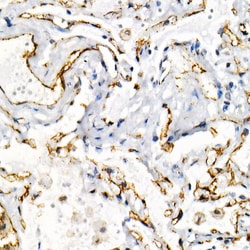

| ELISA, Immunohistochemistry (Paraffin), Western Blot, Immunocytochemistry | |